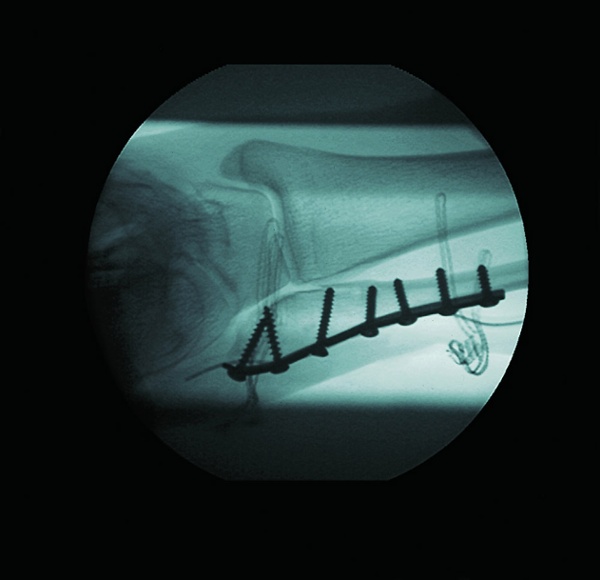

Clinical & System Images